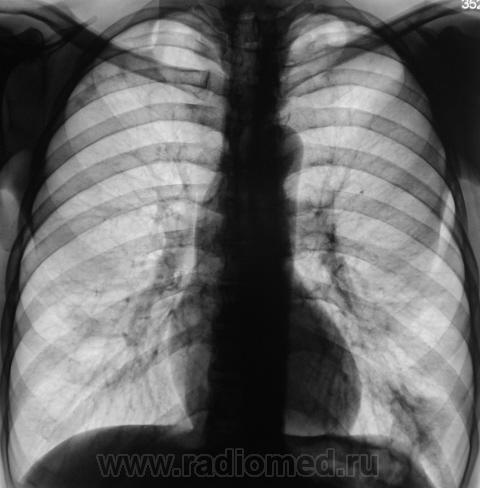

Пациент, как чаще бывает, взят на контроль дообследован и отправлен к фтизиатру с диагнозом (предварительным) - очаговый туберкулёз.

Томографируем.

Конечно, берем на "контроль".

Зову коллегу фтизиатра. Коллега, весьма эмоционально вспоминает "свою маму", да и "маму пациента", что варнякает об инфильтративном, и о том, как такое могло статься, посылает пациента в областную контору, где все утверждается, пациент стационарно получает лечение.

Прошло достаточное количество времени, и сегодня пациент пришел на плановое рентгенологическое исследование. Снимки ниже.